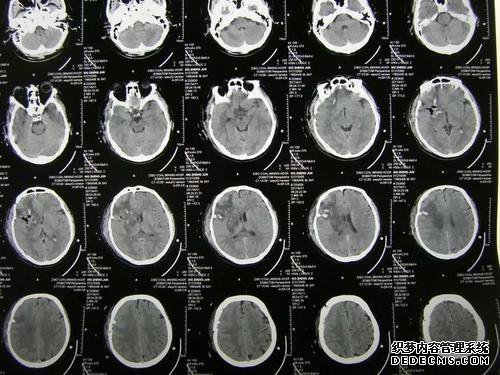

颅骨的CT扫描是轴向位置,即从上到下或从下到上切割。每个图像厚5毫米。换句话说,可以在图像中以5mm的厚度显示头部组织。

颅骨计算机断层摄影胶片由多个图像组成。第一图像通常是外耳道和眼extra外线的最低层。最后一个图像是头部的顶部,通常为24和25层。

头部CT分为两个窗口。第一个窗口是软组织窗口,脑组织的外层是白色圆圈,头骨,头骨内部的灰色区域是脑组织。

脑组织中也有黑色部分。蛛网膜下腔的传统结构是沟和脑池。由于是脑脊液,因此屏幕是黑色的。

对于创伤后CT扫描,通常使用骨骼窗口的第二个位置进行显示。这主要表明头骨是透明的白色脑组织。